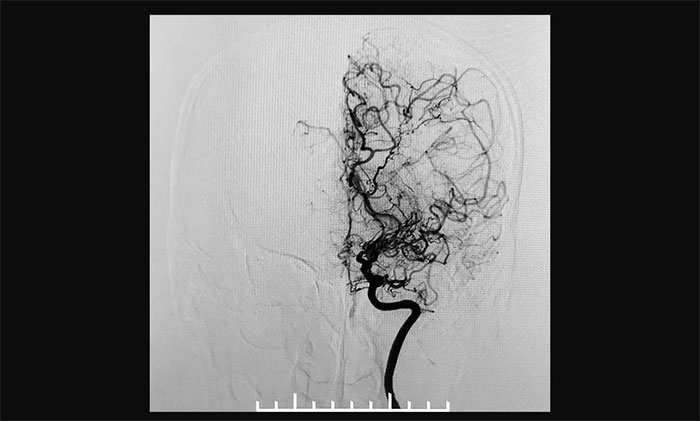

▲异常血管网在脑血管造影时形似“烟雾”

上海蓝十字脑科医院神经外科6A病区专家宫卫东主任介绍,烟雾病又称“自发性脑底动脉环闭塞症”,是一组以双侧颈内动脉末端和(或)大脑前动脉、大脑中动脉起始部缓慢进展性狭窄以致闭塞后,脑底出现代偿性异常血管网为特点的脑血管病,因其血管造影形似“烟雾”,故称为“烟雾病”。

近年来,随着经颅多普勒超声、CT、磁共振以及数字减影血管造影(DSA)等影像学技术的逐渐发展和普及,在我国,烟雾病不再罕见,确诊率也呈逐年增高的趋势。